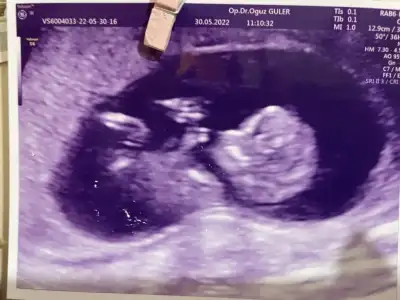

Bende merak ettim bana da bir bakar mısınız? Bugün gittim doktora henüz öğrenemedik 😊 12+5 karından bakıldı

89BACFD2-6748-4B88-946E-5142EC24D3AE.webp

Mehaba,

Bizim için bir defa kız bir defada erkek yorumunda bulunmuştunuz, haftaya cinsiyet öğreneceğiz bizim görüntümüzü tekrar inceler misiniz cinsiyeti öğrenince mutlaka dönüş yapacağım :) Ultrason karından görüntü

• 7 haftalık.webp

7 haftalık.webp

48,3 KB · Görüntüleme: 73